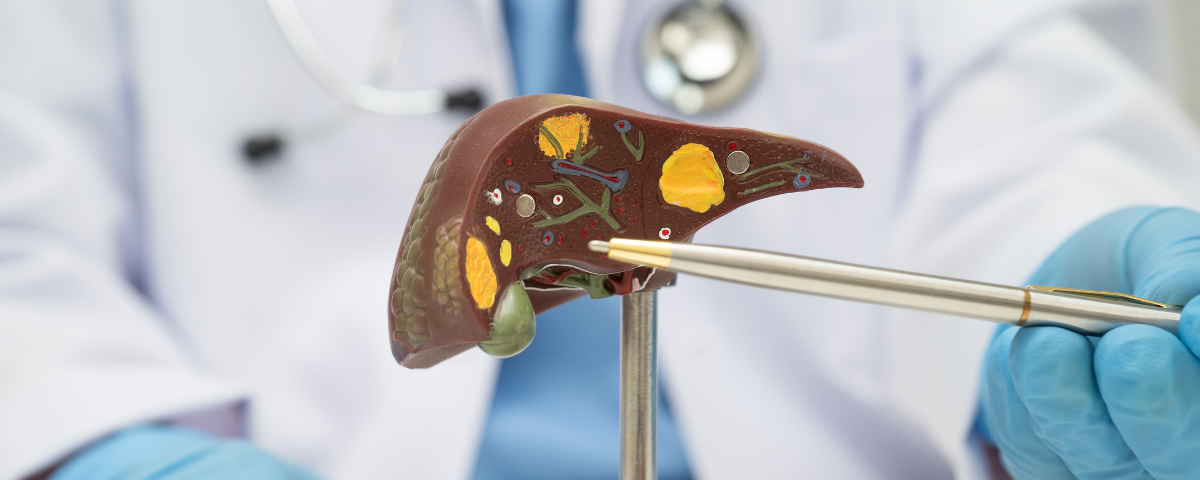

Vesícula biliar e bile

O fígado produz a bile, líquido que fica armazenado na vesícula biliar e participa da digestão das gorduras e na eliminação de algumas substâncias pelas fezes, como metabólitos, excesso de colesterol e compostos tóxicos. Sempre que o animal (ou nós) se alimenta, a vesícula biliar contrai e libera a bile no intestino.

O que é lama biliar?

Acredita-se que a lama biliar, uma forma mais densa da bile, se forme porque a vesícula perde sua capacidade normal de contração e escoamento da bile, e também por um desequilíbrio nos elementos que compõem a bile – em especial, sais de colesterol, ácidos biliares e muco que a própria parede da vesícula secreta, tornando-a mais densa e difícil de escoar. Em geral, nos preocupamos quando ela ocupa metade ou mais do espaço da vesícula biliar e é imóvel.